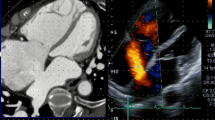

Real-time fusion of two or more cardiac imaging modalities of the beating heart is not a simple task. The key feature to enable correct real-time fusion is the co-registration of the echocardiography probe position with the intervention table and the angulation of the fluoroscopy C-arm [18, 33]. Special software is needed to recognize the TEE probe within the field of fluoroscopy view and to align its position with that of the C-arm. Once co-registration is successfully performed, the TEE probe and the fluoroscopy arm can be moved while image fusion is maintained (Fig. 3). Markers (dots or crosses) can be set to highlight important structures on the echocardiography image, and they are automatically displayed and updated in real time on the fluoroscopy image (Fig. 4a). Figure 4b demonstrates why the default image orientation of different imaging modalities can be confusing and how overlay imaging assists SHD teams in overcoming such challenges. The ability to overlay color Doppler images additionally facilitates the identification of specific targets, improving the rapid, accurate identification of structural lesions.

Tools in fusion imaging: markers (a) and overlay imaging (b). During the MitraClip intervention, the main mitral lesion can be labeled by the echocardiographer using a marker (red dot placed on the mitral valve). This marker is automatically demonstrated in real time on the fluoroscopy image (a). Using the overlay mode (b, showing an atrial septal defect), the echocardiographic image is overlaid on top of the fluoroscopy image in the correct position and angulation. The interventional cardiologist can choose between the purple and the green echo views given by xPlane echocardiography. In this case, the green view better demonstrates the anatomy for puncture purposes. The overlay mode highlights the orientation difficulties that SHD teams face during an intervention. In the modified TEE bicaval view, the superior vena cava is located to the right, while the coronary sinus is to the left, connected by the horizontally orientated interatrial septum. During fluoroscopy for transseptal puncture, the orientation of the C-arm is mostly neutral (in our example, LAO 13.5°, CRAN 0°). This leads to a completely different orientation: the superior vena cava is cranial, while the coronary sinus is at the bottom and to the lateral, with a more or less vertical interatrial septum. SVC, superior vena cava; CS, coronary sinus; IAS, interatrial septum. Blue arrow: depicting the left ventricular lead in the CS. a Adapted from Sündermann et al. [32••]